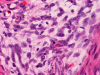

The excised mass is composed of an intermingled arrangement of mature adipose tissue, densely packed primitive spindle cells with small amount of cytoplasm, and mature appearing spindle cells with substantial amount of cytoplasm that gives the appearance of smooth muscle (Panel  A). Abrupt transition between the three elements are common (Panel B). The densely packed, small primitive spindle cells have elongated, cigar-shaped nuclei with amphophilic cytoplasm. Pleomorphism and mitotic figures are not seen. A small number of lymphocytes are present among these cells (Panel C). In areas with appeance of smooth muscle, the cells have elongated, sometime wavy nuclei without significant pleomorphism or mitosis (Panel D). Areas with thick, wavy collagen fibers admixed with benign appearing spindle cells are also present (Panel E and F) and some of these areas are more loosely packed than the other areas which may mimic the appearance of a neurofibroma. In contrast to other areas, these collagenous areas merge imperceptibly with the more cellular areas. In some of the densely packed spindle cell areas, there are small packets of loosely packed cells that give a myxomatous morphology on high magnification (Panel G and H).